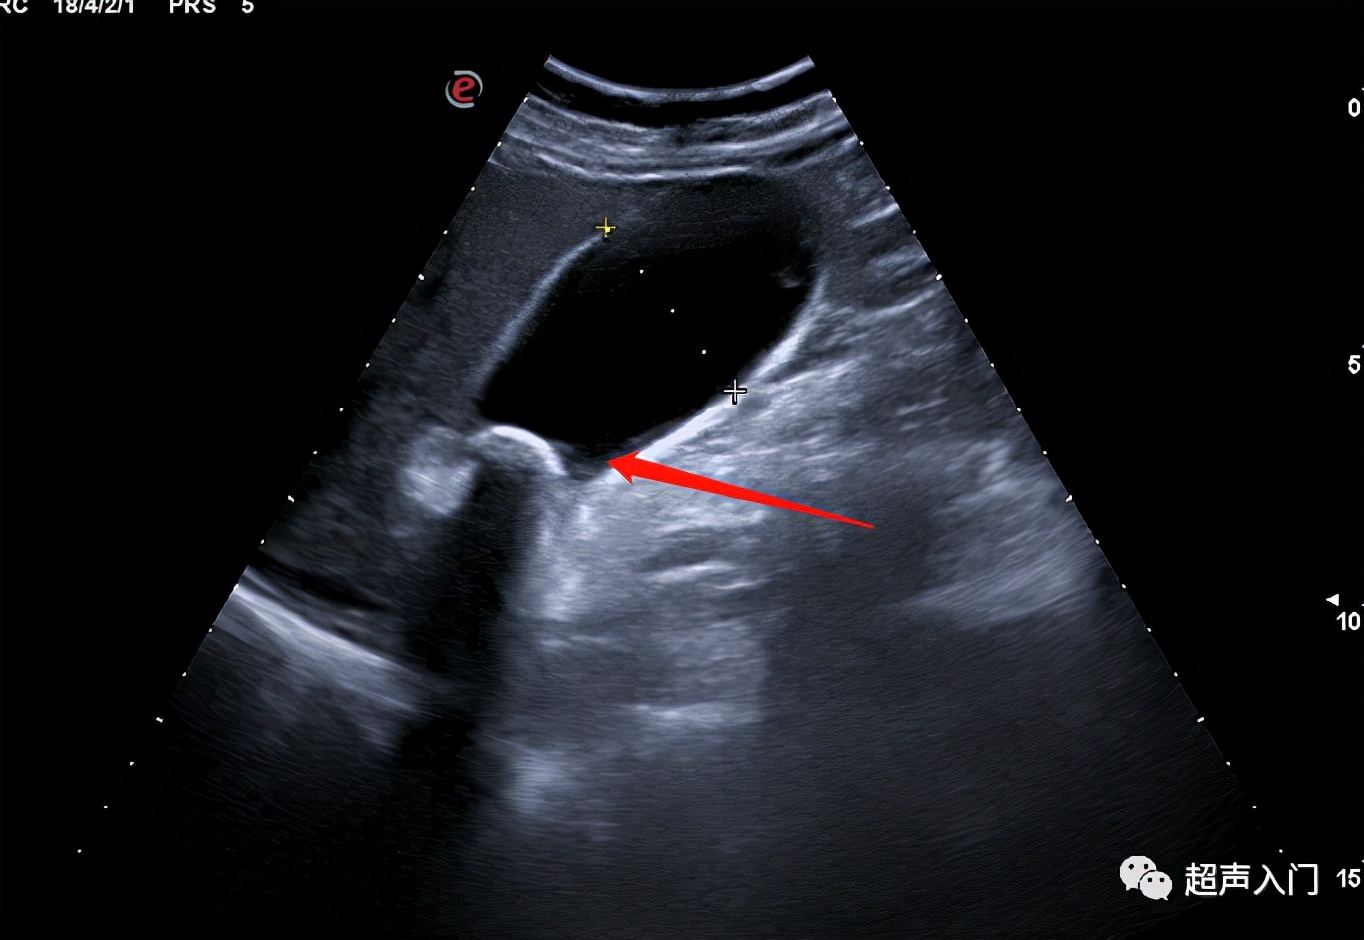

08 胆囊息肉

(胆囊上的肉疙瘩)